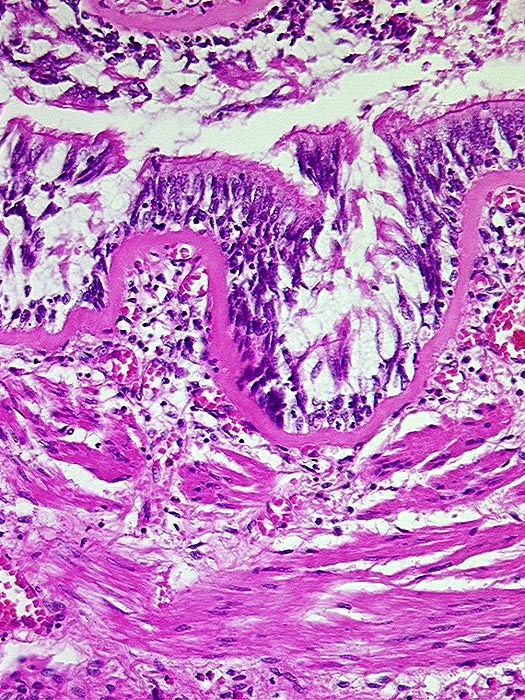

Asthma bronchiale

Bronchiolus mit starker Verdickung der Basalmembran und der glatten Muskelschicht.

Tod im Asthmaanfall bei bekanntem Asthma bronchiale.

Histologie